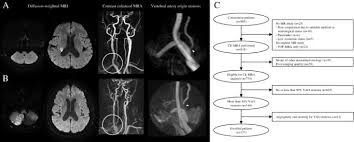

Vertebral artery occlusions fall under the umbrella of Vertebrobasilar Disease VBD otherwise known as Vertebrobasilar Insufficiency VBI. However data on the treatment of posterior circulation stroke are less clear. The optimal treatment for the non-acute intracranial vertebral artery occlusion NA-ICVAO in patients at high risk of stroke despite the best medical treatment remains unclear.

We performed a prospective observational study using a single stroke center registry to investigate the risk of recurrent stroke and vascular outcomes in patients with. Occlusion of the Vertebral or Basilar Artery Follow Up Analysis of Some Patients with Benign Outcome Louis R. Variable restenosis rates have been reported in the literature with small improvements demonstrated using drug eluting stents.

Reference - ASAACCFAHA guideline on the management of patients with extracranial carotid and vertebral artery disease mnh 21471149 p aph 59955487 p a9h 59955487 p byh 59955487 p beh 59955487 p bmh 59955487 p cxh 59955487 p mdc 21471149 p Vasc Med. However data on the treatment of posterior circulation stroke are less clear. SUMMARY Ten patients with angiographically verified occlusion of the basilar or vertebral artery have been followed for an average of 275 years. Occlusion of the Vertebral or Basilar Artery Follow Up Analysis of Some Patients with Benign Outcome Louis R. Variable restenosis rates have been reported in the literature with small improvements demonstrated using drug eluting stents. Endovascular treatment of vertebral artery stenosis VAS is a safe and effective technique for treating symptoms caused by posterior circulation ischemia with high technical and clinical success rates low complication rates and durable long-term results. Clinicians must carefully balance the risks of surgery versus the limitations of endoluminal intervention before proceeding.